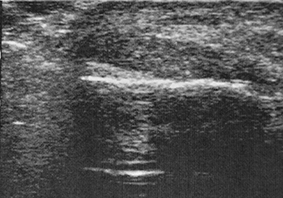

La aponeurosis plantar es más gruesa en pacientes con fascitis, grosores de 4,95 a 6,1 mm frente a 3,22 a 4,0 mm en sujetos sin patología [41][42]. El engrosamiento de la fascia ≥4 mm se asocia con la fascitis plantar, aunque también se ha encontrado en el 21% de los casos asintomáticos [43].

El grosor de la fascia es fundamental para indicar la cirugía en la fascitis [44]. Una fascitis plantar con un grosor ecográfico superior a 4 mm no mejorará con ningún tratamiento conservador y ningún paciente debería ser intervenido con un grosor de la aponeurosis plantar inferior a 5 mm [45].

La fascitis plantar es una patología de las partes blandas y su diagnóstico no se puede basar únicamente en la imagen radiográfica de un espolón del calcáneo o calcificaciones bien estén en la inserción del tendón de Aquiles o en el origen de la fascia plantar [46]. Por eso, la ecografía es el método de diagnóstico de referencia para la evaluación de los trastornos de la fascia plantar [47], pues su precisión y fiabilidad son comparables a la RM y es más rápida, económica y accesible [30][44-49] (Figura 2)

Figura 2. A) Imagen ecográfica de la aponeurosis plantar. B) medición del grosor de la aponeurosis plantar. C) RM sagital del pie